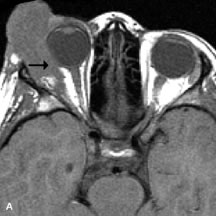

MRI is particularly helpful in the detection and characterization of subperiosteal hematomas of the orbit (Fig. 19). They are most commonly seen in the subperiosteal space of the superior orbit as well-defined masses following a traumatic injury. The signal intensity varies depending on the acute, subacute, or chronic nature of the hematoma, based on the stage of blood degradation. Fresh hemorrhages are hypointense on T1-weighted images and hyperintense on T2 images. Hematomas that are 1 to 7 days old are hypointense on both T1- and T2-weighted images. T1-weighted images of hematomas more than a week old are hyperintense due to the oxidation of deoxyhemoglobin to methemoglobin, whereas the T2 images remain hypointense.63

Fig. 19. A. T1- and (B) T2-weighted MR scans demonstrate a large acute subperiosteal hematoma (H) that lies between the cortical bone of the orbital roof and the inferiorly displaced periorthira (double arrow). The extracopal fat (arrow) and levator muscle are displaced inferiorly.